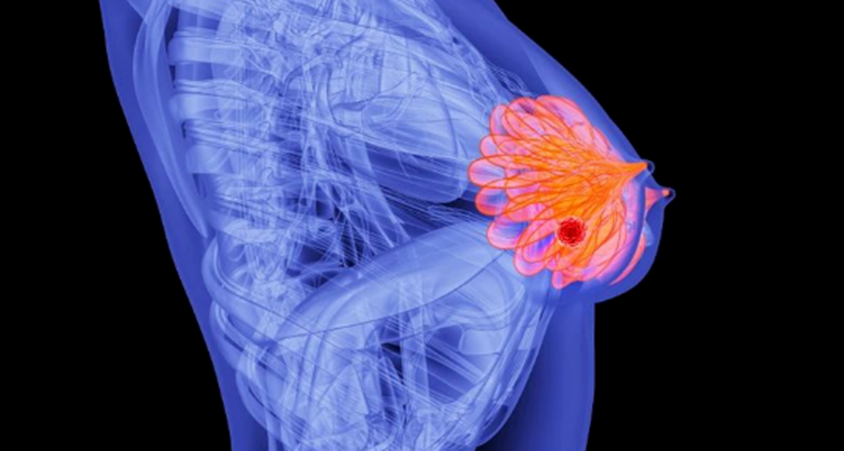

刚刚,晚期乳腺癌新药获批上市,肿瘤缩小率翻倍!耐药难题被破解?

对于激素受体阳性的晚期乳腺癌患者来说,内分泌治疗是毋庸置疑的“主力大将”。可惜的是,时间一长,部分患者会为基因突变(特别是 ESR1突变)导致耐药——药不灵了,肿瘤开始肆意进展。

在乳腺癌当中,有一种常见的类型被称为激素受体阳性(HR+)乳腺癌。这类癌症的癌细胞上有一类“天线”(雌激素受体),能接收到雌激素信号,从而不断获得生长动力,促进肿瘤进展。

而 Imlunestrant的作用,是直接将携带ESR1突变的癌细胞上面的天线摧毁,此后癌细胞彻底无法接收到生长信号了。